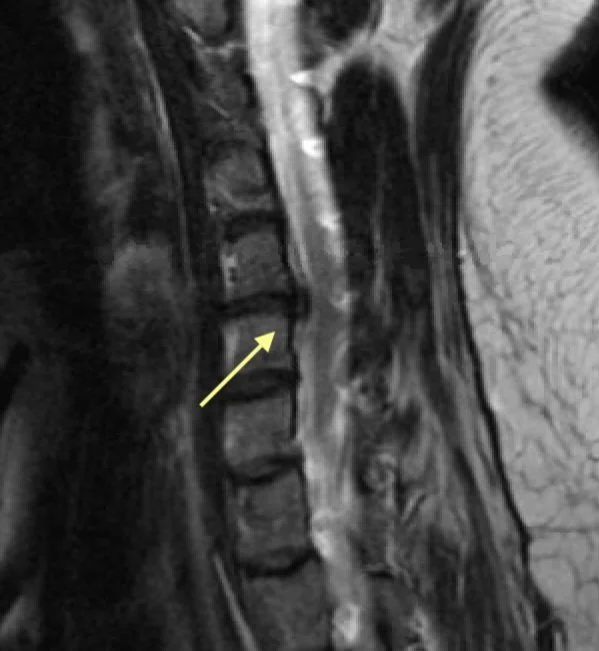

Lumbar MRI disc herniation nerve root compression

This MRI cross section of the lower back shows a large disc bulge (arrow) that is compressing the S1 nerve. This patient improved with conservative measures.